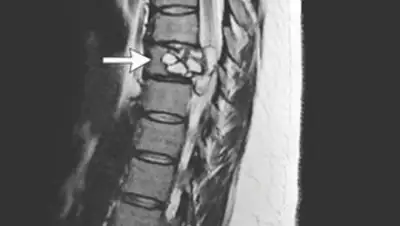

Магнитно-резонансная томография показала поражение в районе девятого грудного позвонка, частично располагающееся на мембране, покрывающей спинной мозг. Пациентку прооперировали.

Удаленный объект оказался кистой, которая выросла в результате проникновения в позвоночник ленточного червя Echinococcus granulosus — эхинококка. Этот паразит может заразить человека, если проглотить его яйца. Личинка рождается в кишечнике, затем попадает в кровь и заносится в печень или другие органы.